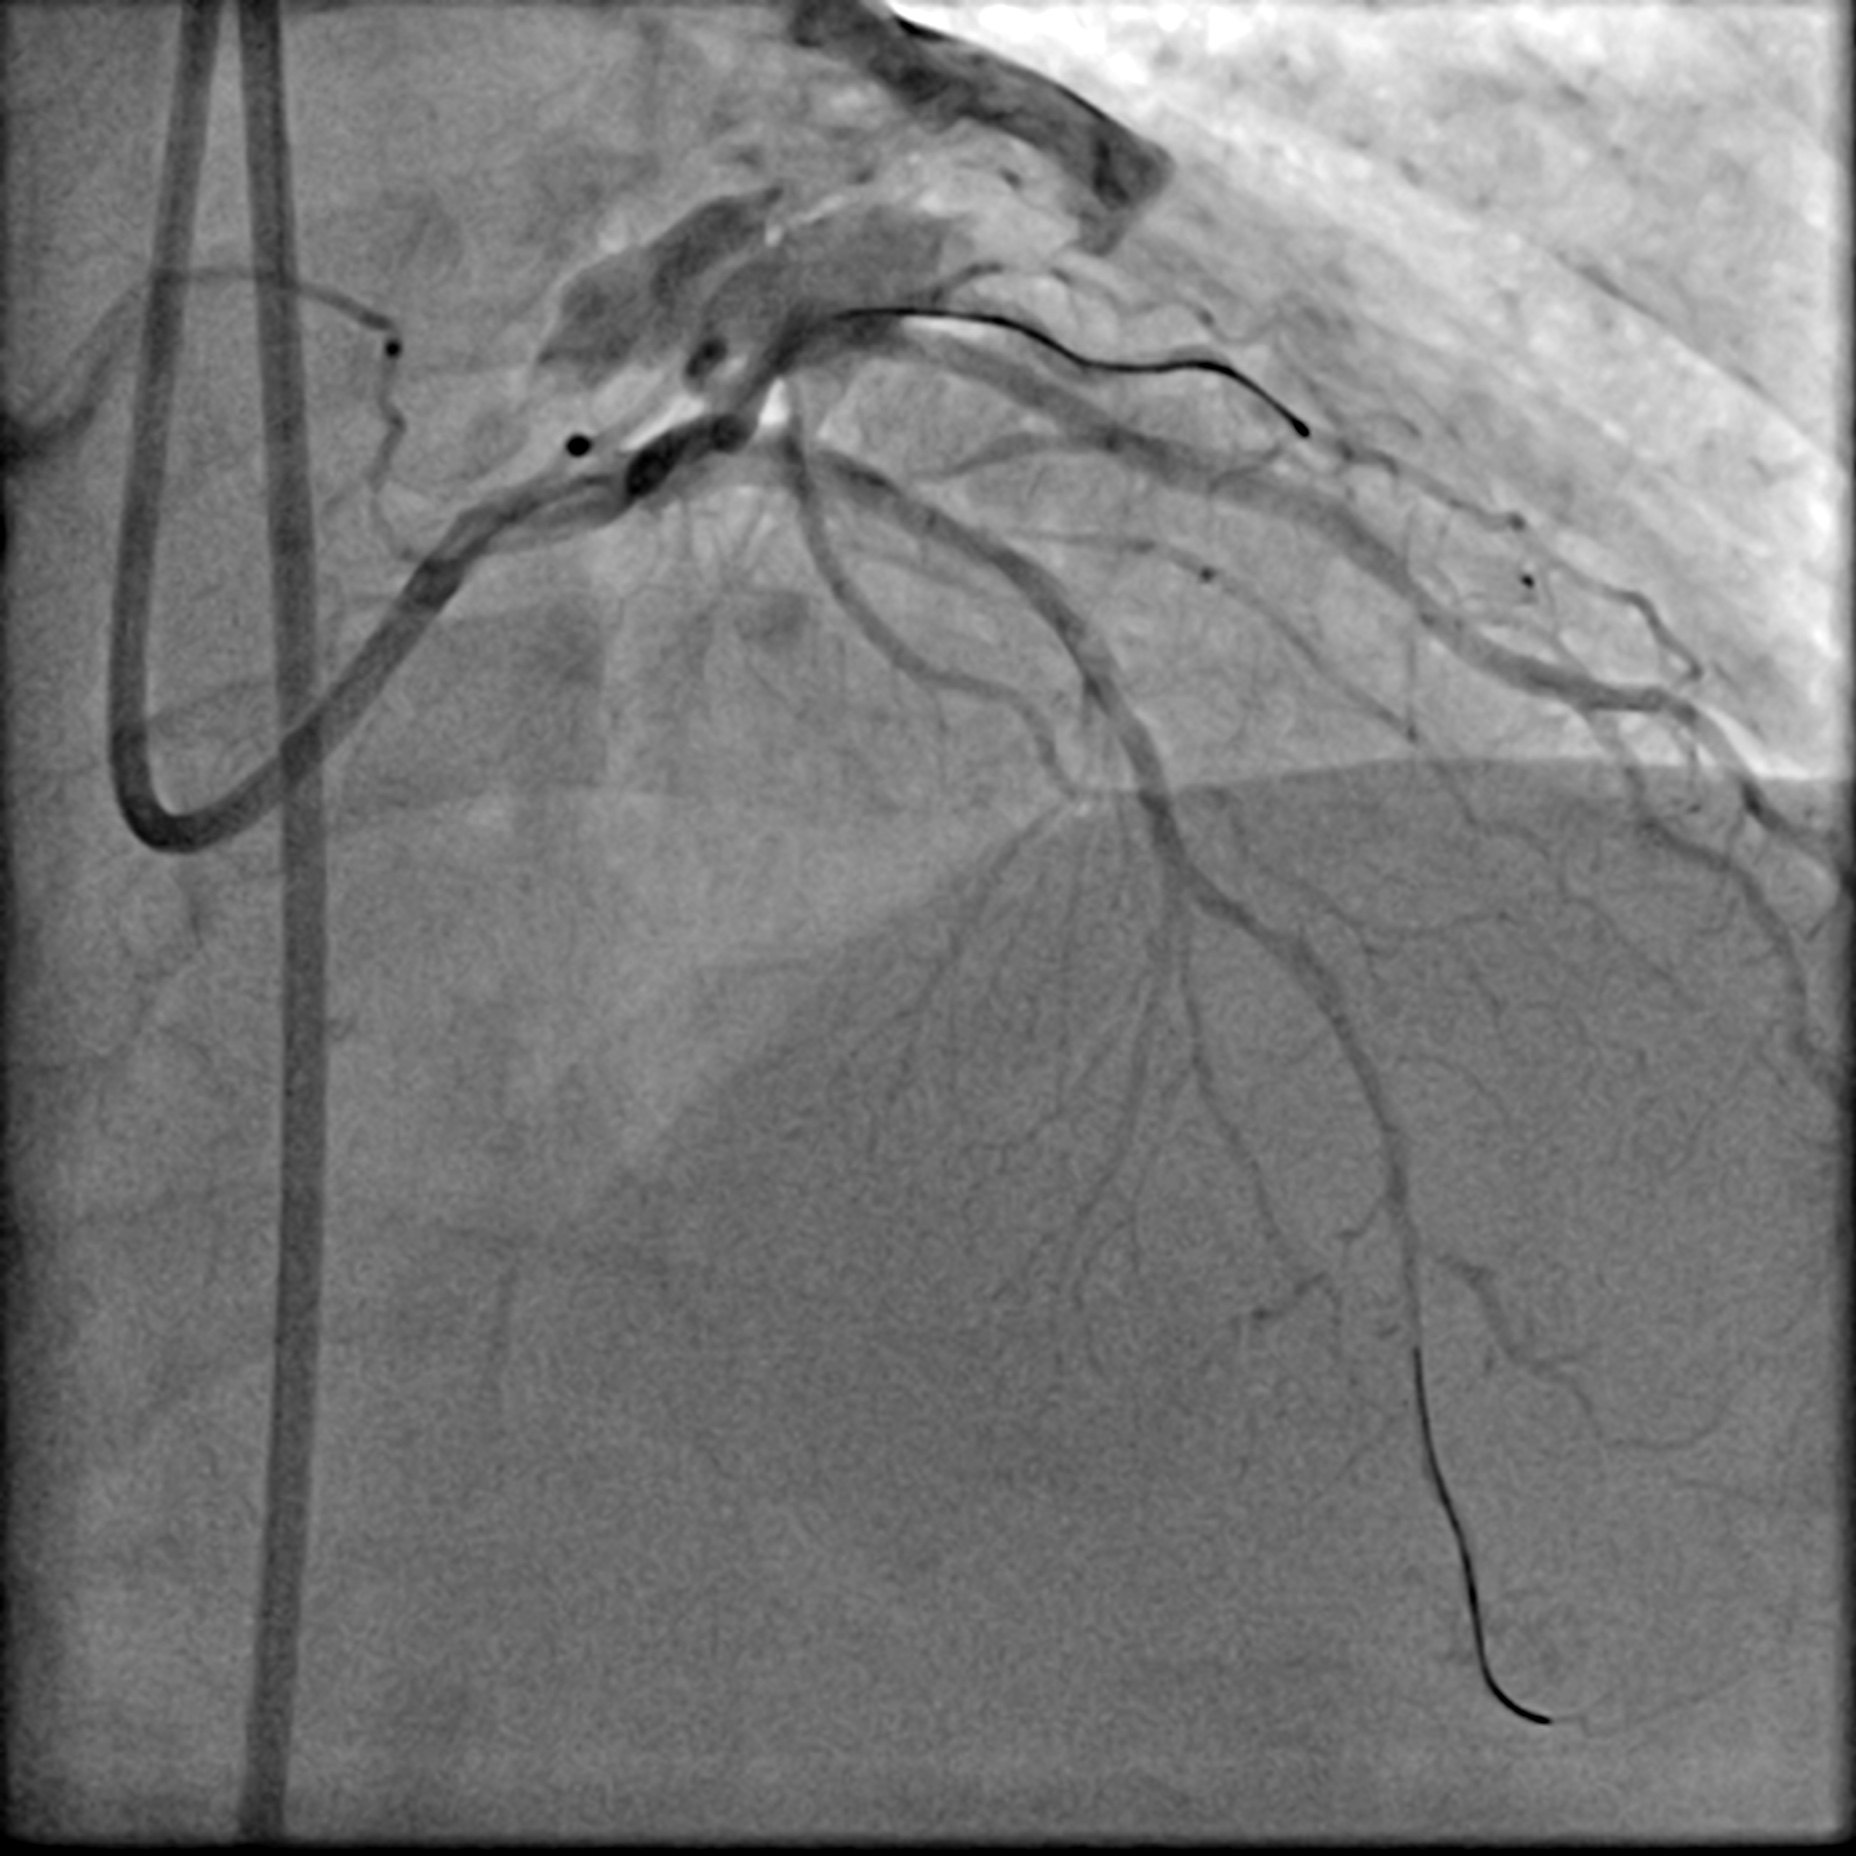

After positioning the ViperWire in the distal LAD, the OAS was delivered, and calcium debulking at low speed was performed safely. Afterward, the LAD was pre-dilated with a 2.5 mm scoring balloon and a 3.5 mm cutting balloon, while the LCx was pre-dilated with a 3.0 mm cutting balloon. A repeat angiogram revealed an Ellis 3 perforation in the proximal LAD, accompanied by a drop in the patient's blood pressure. Expeditiously, a 3.0 mm balloon was inflated at the perforation site, and its location was confirmed with an angiogram, which indicated immediate reduction of the perforation. A pigtail catheter was inserted simultaneously under echocardiographic guidance, and autologous blood transfusion was initiated. The perforation was covered with a 2.5 mm x 20 mm covered stent and post-dilated with a 3.0 mm NC balloon. This reduced the leak, but significant flow persisted. IVUS showed a gap between the stent strut and vessel wall near the LAD carina, allowing for persistent leakage. The covered stent was further post-dilated with a 3.5 mm NC balloon and a hugging balloon technique using two 2.5 mm balloons. These measures failed, as the maximal expansion of the 2.5 mm covered stent is limited to 3.0 mm. A Kissing Balloon Technique (KBT) was attempted at the bifurcation, but it proved futile. Finally, a second 3.5 mm covered stent was placed proximally, which successfully sealed the perforation, leaving only a trivial leak. The hemoperricardium resolved after 24 hours.